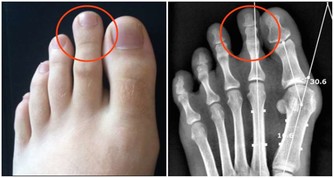

後來到另一家醫院檢查,最後確診為圓錐角膜。

圓錐角膜的最終結果就是角膜移植,

或者說,角膜基質的厚度必須保留250以上,否則就會出現圓錐角膜。

因而角膜會逐漸變尖,最終形成圓錐角膜,圓錐角膜的後果是使視力永遠喪失。